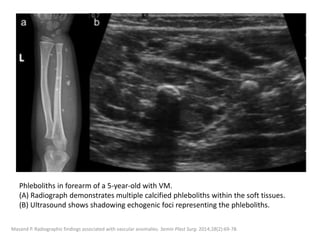

Phleboliths in forearm of a 5-year-old with VM.

(A) Radiograph demonstrates multiple calcified phleboliths within the soft tissues.

(B) Ultrasound shows shadowing echogenic foci representing the phleboliths.

Masand P. Radiographic findings associated with vascular anomalies. Semin Plast Surg. 2014;28(2):69-78.